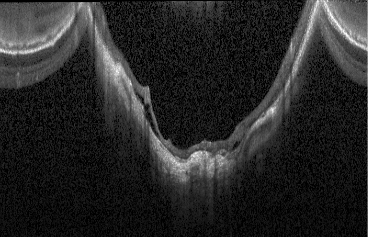

Images - The scanning laser ophthalmoscopy (SLO) image

- The segmentation data for different retina layers (ILM, RPE) when provided in the HEYEX Raw file